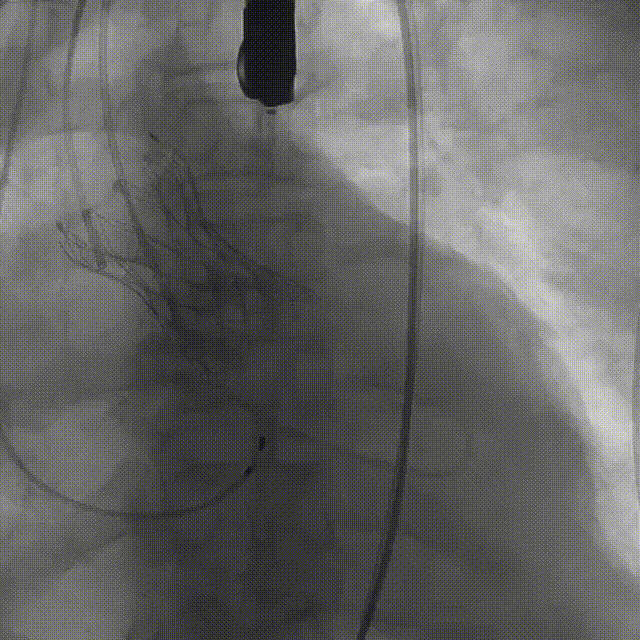

手术影像:

左冠造影灌注良好

右冠造影灌注良好

主动脉根部造影,狭窄伴反流

导丝顺利跨瓣

23mm球囊预扩无腰征,微量漏

输送器柔顺过弓、跨瓣

瓣膜开始零位定位

瓣膜逐步释放到工作位

工作位造影位置良好

瓣膜逐个脱钩

完全释放后造影,膨胀不良,有漏

25mm球囊后扩

后扩后瓣膜形态良好,造影基本无漏

外周血管造影检查良好